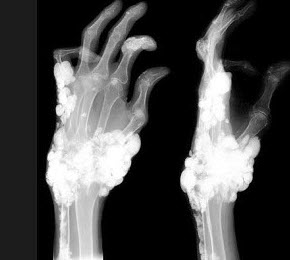

D.消化道穿孔

107、单项选择题

女,79岁,双手肿块,疼痛,结合图像,最可能的诊断是()

A.骨脓肿

B.骨囊肿

C.骨结核

D.原发性肿瘤样钙质沉着症

E.骨肉瘤